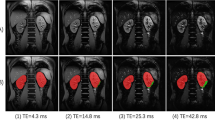

All participants in this study completed the MR exam and no images were discarded after the preliminary visual inspection. The image quality is also confirmed with the control report (Supplementary Fig. S2) where both absolute and relative subject movement was always <1.5 mm. An example of HASTE and DTI-derived parametric maps is shown in Fig. 1. Moreover, an example of the tractography reconstructions from DTI without processing and from topup-s2v pipeline is reported in Fig. 2.

Acquired and processed images of a 28-year-old female volunteer. (a) HASTE image; (b–f) b0-image, an enlargement of b0-image and parametric maps (from left to right: FA, MD) obtained with different image processing pipelines ((b) without processing; (c) eddy; (d) eddy-s2v; (e) topup; (f) topup-s2v). A kidney region (corresponding to the red box in b0-image) was zoomed to highlight the differences of the results between the processing pipelines.

The obtained parametric map values are consistent with those presented in kidney DTI studies of healthy volunteers for similar acquisition protocols and age range14,21,32,48,49,50. Moreover, as pointed out in Fig. 3, FA and AD values are considerably higher in medulla respect to cortex and, conversely, MD and RD values are higher in cortex respect to medulla. The obtained results, confirmed for all processing pipelines, are in line with those presented in literature15,16,33. The radial orientation of tubules in the renal medulla produces more restricted movement of the water molecules respect to cortex and, as a consequence, FA and AD (the preferential diffusion direction and the diffusivities perpendicular to the principal diffusion direction, respectively) maps result in higher values in the medulla than the cortex. Conversely, since MD and RD parametric maps represent the mean diffusivity and the diffusivity parallel to the principal diffusion direction respectively, it is expected to observe higher values of such diffusivity parameters in the cortex respect to medulla51. According to the results found in literature32,34,50, the overall paired t-test results from right and left kidney in terms of parametric map values show no consistent difference. However, as shown in Fig. 4, medullary AD values carried out both without processing and with eddy-s2v considerably differ between right and left kidney. The unwanted results might be explained by the influence of an improper processing pipeline. The influence of the different processing pipelines is also visually confirmed in Fig. 1 where the image artefacts related to eddy-currents and susceptibility-induced distortions are mitigated in both topup (Fig. 1e) and topup-s2v (Fig. 1f) processing approaches.